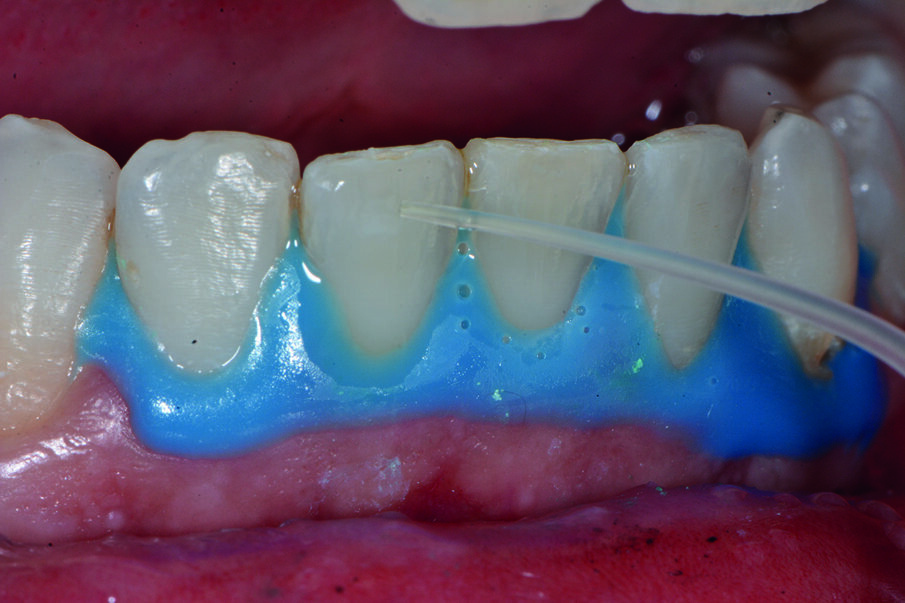

Prima del trattamento abbiamo applicato un rilevatore di placca alla fluoresceina Plac-o-Tect (Directa) per evidenziare la topografia della presenza di biofilm batterico nel cavo orale. Osserviamo la topografia del biofilm batterico presente e condividiamo con il paziente i siti più ritentivi di biofilm batterico in modo da avere una comunicazione non verbale del rivelatore, utile per il rinforzo motivazionale del paziente con l’obiettivo di migliorare l’efficacia dell’igiene orale domiciliare (Fig. 3).

Il trattamento di infiltrazione Icon è costituito da tre semplici passaggi: mordenzare; asciugare; infiltrare. Dopo il pre-trattamento con un gel mordenzante, viene applicato sulla zona da trattare l’infiltrante, una resina estremamente fluida. Per azione capillare l’infiltrante penetra in profondità nelle porosità dello smalto che viene poi fotopolimerizzato. Abbiamo apposto una diga liquida con foto-polimerizzazione Icon (DMG) per rimuovere e mascherare le antiestetiche lesioni brown spots. La resina infiltrante ha un indice di rifrazione della luce simile a quello dello smalto sano e consente di compensare la differenza di rifrazione della luce. In questo modo l’aspetto della lesione infiltrata può essere adattato allo smalto sano circostante. Abbiamo applicato sugli elementi dentali che presentavano aree di demineralizzazione, il mordenzante a base di acido-cloridrico (HCl 15%) Icon e lo abbiamo applicato per 2 minuti (Fig. 8). Icon-Etch mordenzante prepara il dente per essere infiltrato. Il gel di acido cloridrico viene applicato sulla zona da trattare con l’aiuto di uno speciale applicatore per rimuovere lo strato pseudo-intatto della superficie. Solo dopo la sua rimozione l’infiltrante può penetrare nel sistema poroso del dente. Abbiamo lavato le superfici per 30 secondi (Fig. 9) e abbiamo asciugato i denti. Abbiamo applicato Icon-Dry (etanolo 99%) e lasciato agire per 30 secondi e fatto asciugare il prodotto.